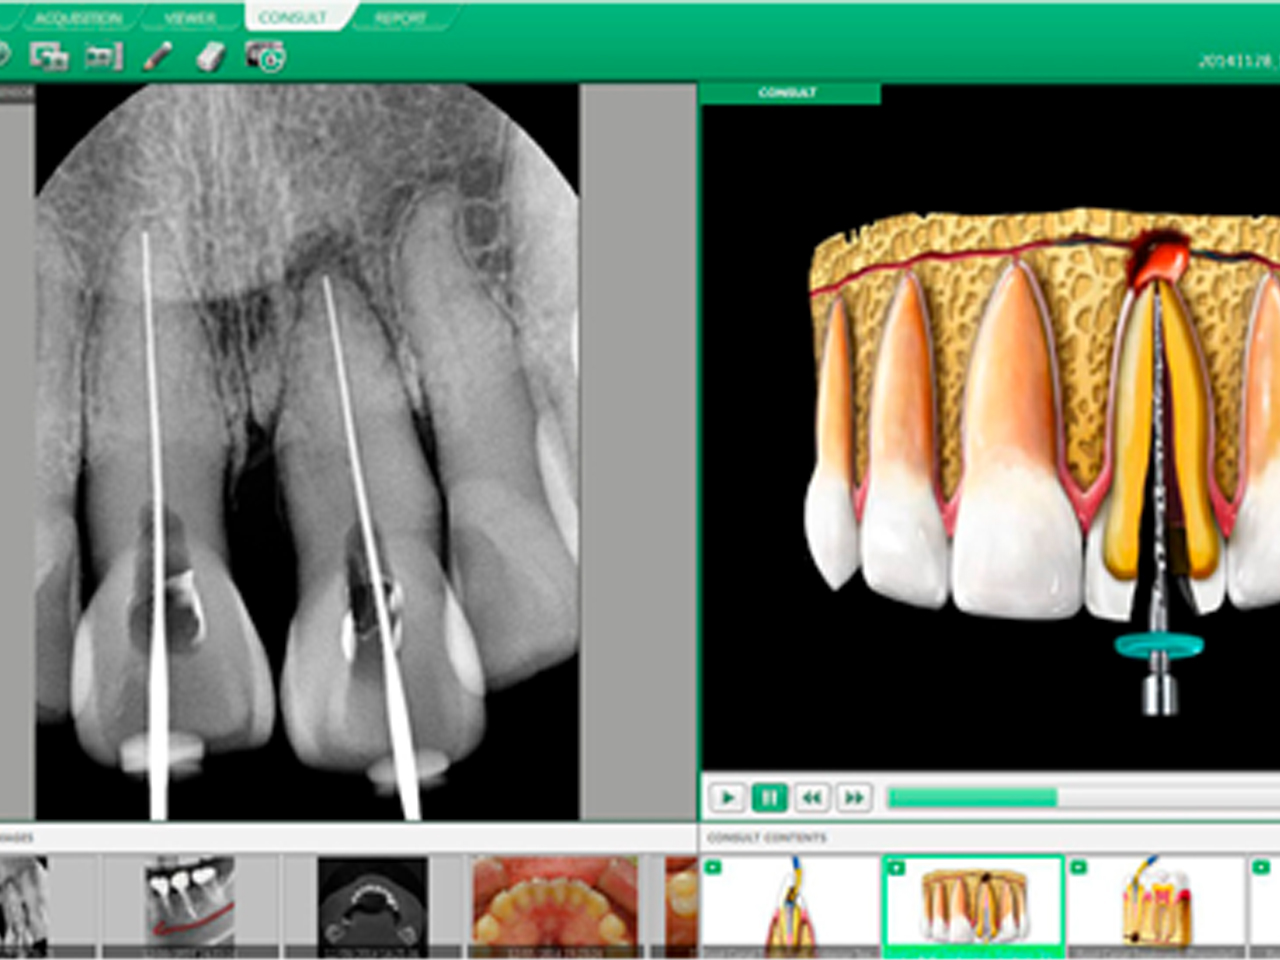

Радиовизиограф (интраоральный визиограф, датчик) – компактное цифровое устройство, позволяющее стоматологу мгновенно получать рентгеновские изображения зубов высокого разрешения и сохранять их в цифровом формате. Датчики подключаются к компьютеру, где снимки сразу же доступны для анализа.

• Алгоритмы обработки: современные программы улучшают контраст и убирают шум, что особенно важно при эндодонтических и пародонтологических исследованиях.

Программное обеспечение

Программное обеспечение определяет удобство работы с пациентами и исследованиями.

На что обратить внимание:

• Удобство интерфейса и функциональность,

• Интеграция с клинической базой и другими видами исследований (КТ, ОПТГ, прицельные снимки),

• Поддержка международного формата DICOM — это обеспечивает совместимость с оборудованием разных брендов.

Некоторые визиографы работают только с «родным» софтом, поэтому важно заранее проверить возможности интеграции.